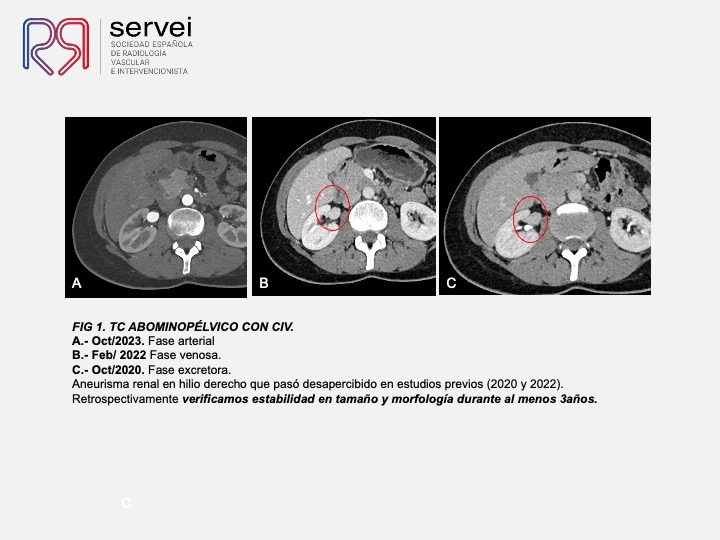

Aneurisma sintomático menor de 2 cm en bifurcación renal. Tratamiento endovascular con dispositivo derivador de flujo (FD)